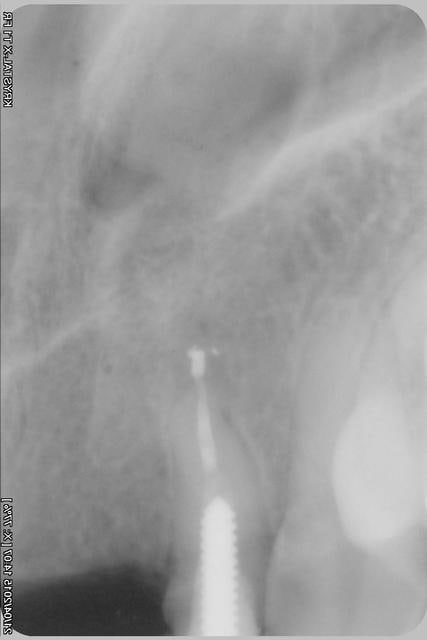

le scan n'est pas terrible, mais suffisant pour voir que 22 une fois extraite, ne va pas etre simple à implanter, par contre 11/21 avec un peu d'expansion...

Des lecross section21 jinha0 - Eugenol

Des lecross section sf6tbl - Eugenol

Des le cross section 12 vyz5ug - Eugenol

Des le cross section 22 w31w6b - Eugenol